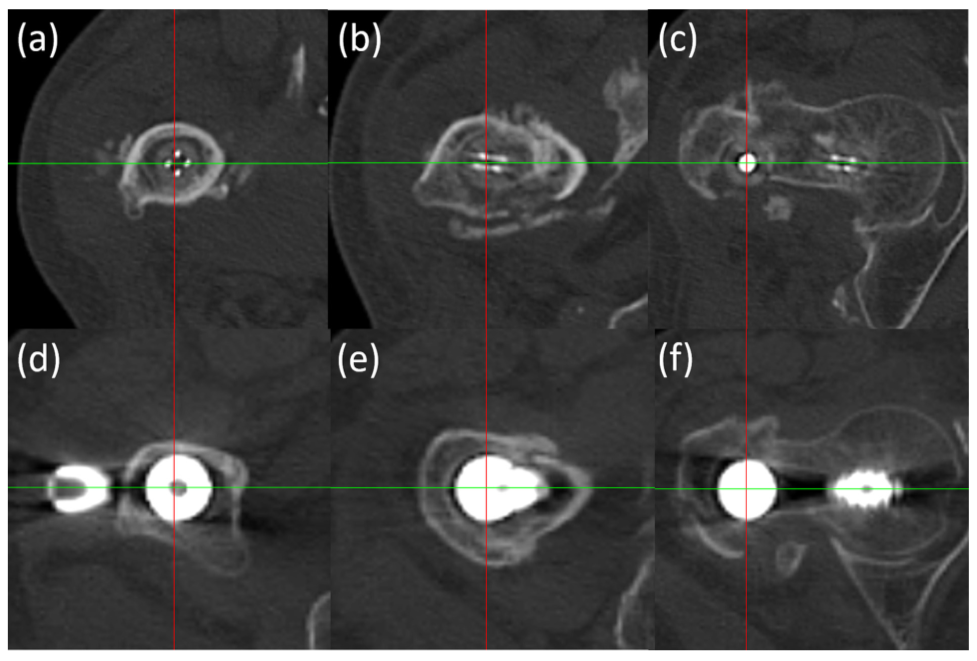

图5 在CT上,金属内植物由于金属散射,导致对骨折线观察存在干扰。

[Results: In the CFR/PEEK group, the fracture site was visible in all zones for all cases except for the posterior zone on the lateral view in one case. In the cranial and middle zones on anteroposterior views and the middle zone on lateral views of the radiographs, the visible fracture site rates in the CFR/PEEK group were significantly higher than those in the metal group. The grades for existence of scattering and effect of scattering on diagnosis of surrounding bone on the CT images were significantly lower in the CFR/PEEK group compared with the metal group.]

与使用传统金属髓内钉治疗的病例相比,使用CFR/PEEK髓内钉治疗的病例在X光片上显示出优越的骨折部位可视性,从而证实了CFR/PEEK髓内钉在评估骨折复位和骨形成方面的优势。CFR/PEEK钉在CT图像上引起的散射很小,导致假体周围松质骨和皮质骨的诊断价值高于金属钉。

[Conclusion: Superior fracture site visibility on radiographs was demonstrated in cases treated with the CFR/PEEK intramedullary nail compared with cases treated with the traditional metallic intramedullary nail, thereby confirming the advantages of the CFR/PEEK intramedullary nail for evaluation of fracture reduction and bone formation. The CFR/PEEK nail evoked little scattering on CT images, leading to higher diagnostic values for the peri-prosthetic cancellous and cortical bone compared with the metallic nail.]